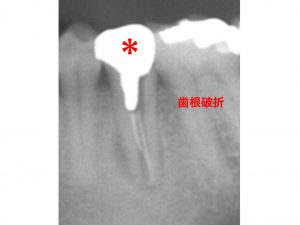

右下の奥歯に問題があった方です。

以下の*印の歯です。

歯肉が腫れ、

歯がグラグラするとのことでした。

診査の結果、

歯根破折していました。

しかも 破折線は、根の先までおよんでおり、

痛みもあるため、保存は難しい状態でした。